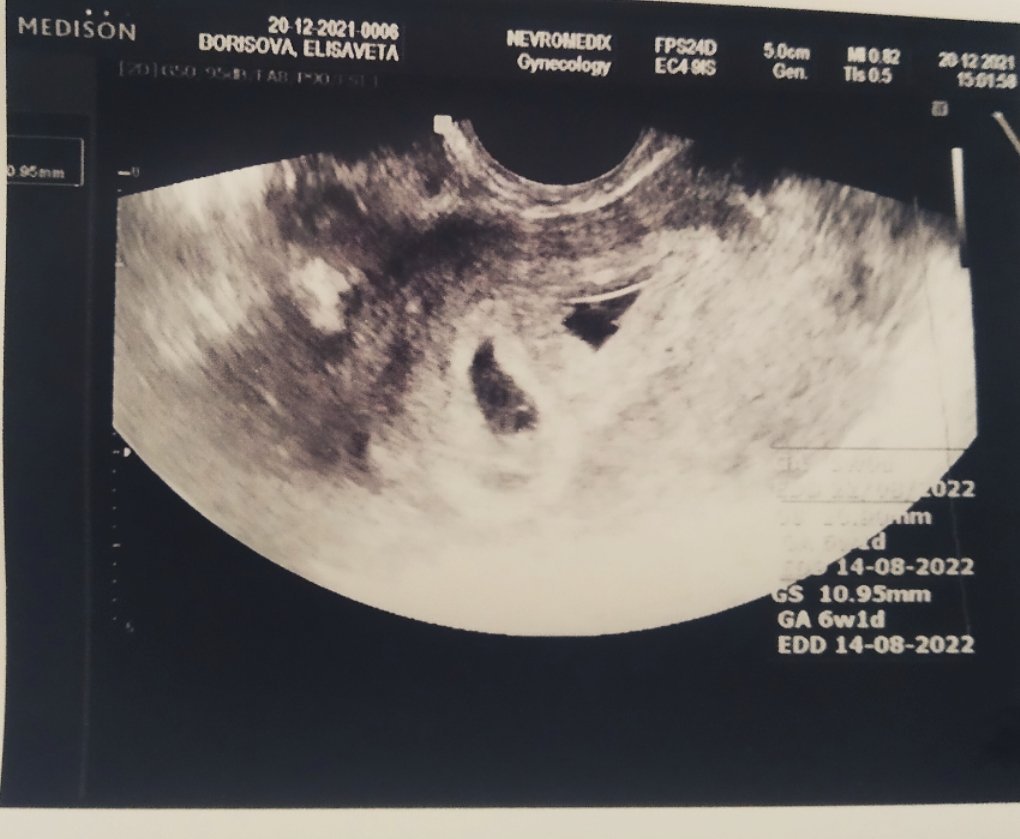

Минавам да споделя , че ходих на преглед, видяха се 2 плодни сака по 10мм , но не и ембриончета (началото на 6г.с.). Викат ме на 04.01 и тогава се надявам да ги видим и чуем, много ми е напрегнато ...

Напълно е възможно да изпаднат в паника момичетата, които са в 6та седмица и не се вижда при тях толкова много. На снимката си е показано 6w/1d.

Да, да, сега видях. В притеснението съм изтървала да видя, че пише. Благодаря ❤️